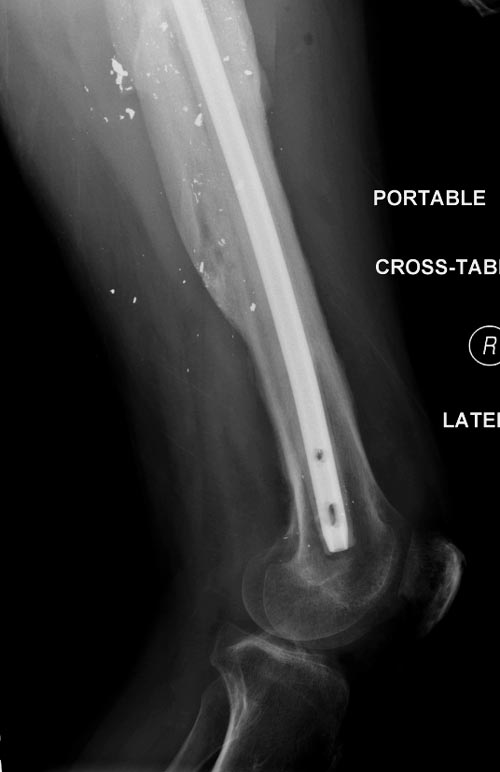

Беспокойство проявил недавно, по поводу жалоб на боли сделано МРТ и

дренирование абсцесса терапевтами. Мы удалили гвоздь, сделали I&D,

рассверливание канала, и ввели гвоздь с антибиотиком. Для гвоздя

использовали стерильную трубку-форму, а антибиотик по 1.0 Tobramycin c

Vancomycin.

В замкнутом без перелома пространстве во время риминга повышается

давление внутри канала, и имеется риск тромбообразования. Для

профилактики и для дренажа - канюлированный винт 6.5 мм в дистальной